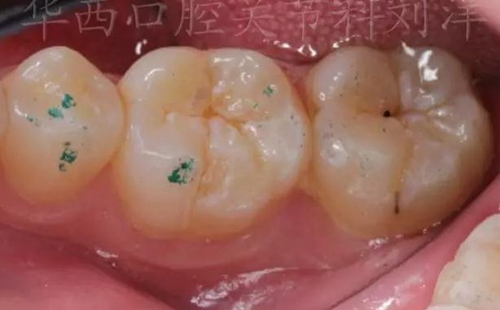

② 然后換用40微米紅色咬合紙,牙尖交錯位咬合

▲圖7:40µm咬合紙

▲圖8:40µm 正中咬合